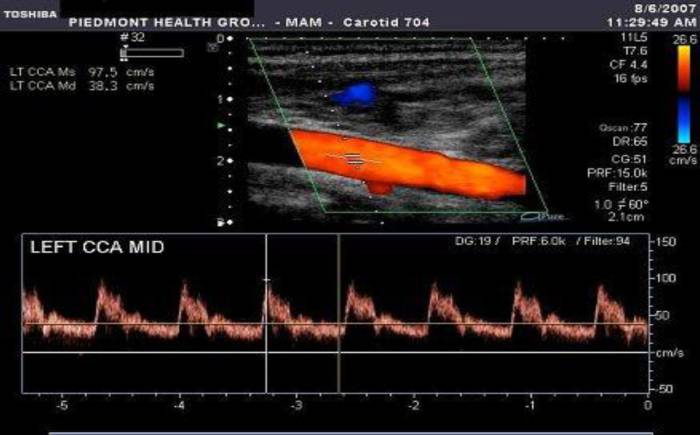

В современное время ультразвуковая диагностика практически любого органа включает в себя исследование его кровотока с использованием режимов, основанных на Доплеровском явлении – это спектральный допплеровский режим в виде графиков скоростей потока крови и цветовой допплеровский режим, представленный в виде цветового окрашивания сосудов. Такую методику называют ультразвуковой допплерографией.

- изучение спектральных характеристик тока крови (максимальную и минимальную скорость, различные специально разработанные индексы).

Также врач проводит сопоставление с нормативными таблицами параметров кровотока, полученных при допплерографии: систолической и диастолической скорости, пульсационного индекса, индекса резистентности. На основании этого делается заключение о сопротивляемости сосуда и косвенно о его проходимости.